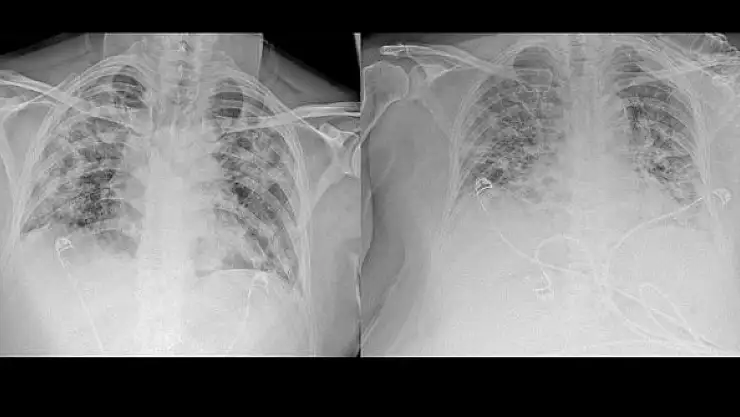

Normal akciğer görüntüleri ile koronavirüs hastalarının akciğer görüntüleri arasında ciddi farklar bulunduğunu belirten Karalezli, şu bilgileri verdi:

"İnsanların aradaki farkları anlamaları için her iki akciğer görüntülerine de yer verdim. Görüntülerdeki beyazlıklar akciğerdeki tutulumu gösteren görüntüler ne yazık ki. Bu hastalar yoğun bakım hastaları. Filmler birbirine az çok benzeyen şekilde. Altta yatan hastalığı olanlarda ise daha kötü seyrediyor."

Kliniğe yeni başvuran bir hastanın, 5 Ağustos'ta çekilen tomografi görüntülerindeki tipik koronavirüs görüntülerinin olduğunu ifade eden Karalezli, hastanın bir hafta içerisindeki tomografi görüntüsünde ciddi değişiklik olduğunu ve enfeksiyonun çok arttığını söyledi.